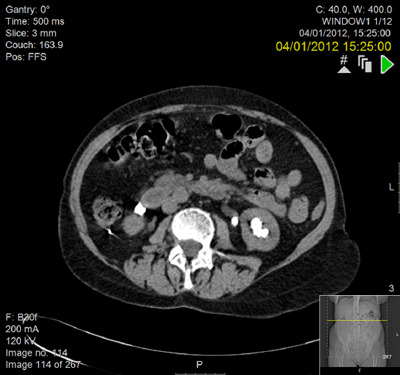

Preoperative IVU and CT demonstrating very little overlying renal cortex in duplex system.

Seven years postoperatively. New left staghorn calculus and right-sided fragment demonstrated outside the kidney.